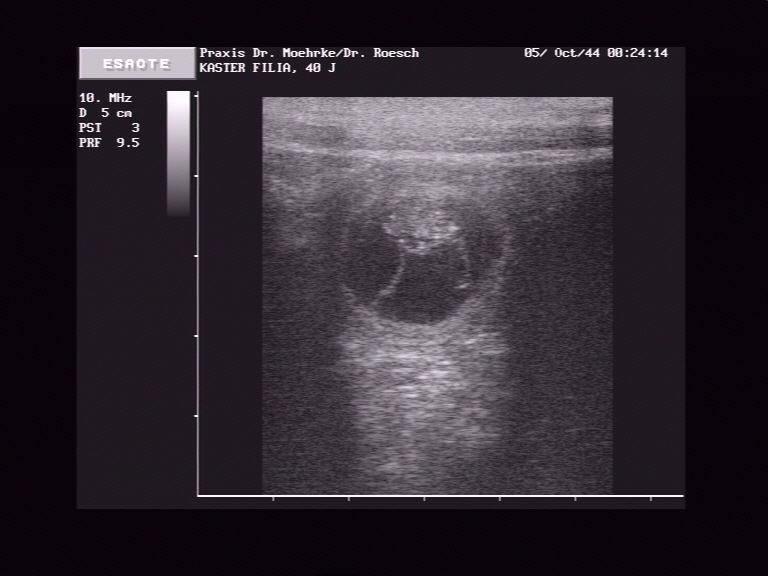

Ultraschall am 16.04.07

*   *

*Datum auf der Aufnahme stimmt leider nicht